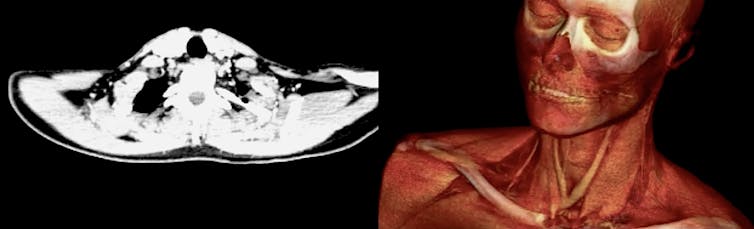

En resumen, un estudiante de Física será potencialmente capaz de enfrentarse a la destrucción de un tumor, catalogar un terreno como huerto eólico, tomar una imagen 3D del SARS-CoV-2 y ayudar posteriormente en la confección de una vacuna, datar un yacimiento arqueológico, encontrar nuevos materiales plásticos para una rodilla artificial, ordenar una serie de números en un computador cuántico, estimar la cantidad de grasa de un alimento mediante rayos-X, motivar y entusiasmar a una clase de 2º de la ESO, autentificar un Goya, predecir la trayectoria de un huracán y, por qué no, calcular la revalorización del Yuan el día de Navidad.

El área de Ciencias de la Tierra también ha ganado notable protagonismo en la disciplina que nos ocupa. Asignaturas como Oceanografía, Ecología, Meteorología, Geofísica, Energías Renovables, Teledetección, etc. son solo algunos ejemplos. La esfera de las Ciencias de la Salud, con materias como Biofísica, Física Médica, Física Forense, Radioprotección, Acústica e Imagen Médica forman ya parte del abanico de competencias en las que un egresado en Física puede (o incluso, debe) desenvolverse.